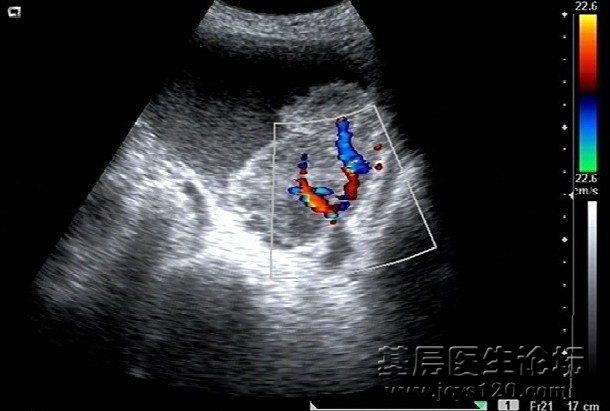

女,77岁,尿频,尿急,尿痛三月余。尿检:白细胞2+,潜血3+ ,血常规正常, 膀胱图片患者 谢谢各位的回复 这位患者超声我提示 膀胱癌拌尿液浑浊 在省级医院病理检查是膀胱癌 诊断依据:膀胱内强回声团内 ... 阅读全文>